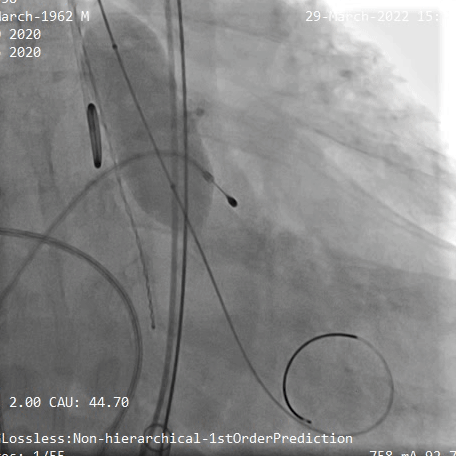

TaurusElite输送系统轻松过弓、跨瓣,AV29瓣膜瓣环下0mm定位释放,到工作位后造影显示瓣膜形态、位置良好

瓣膜定位

释放到工作位观察

释放脱钩后瓣膜形态、位置良好,冠脉血流灌注正常,无瓣周漏,弓部血管造影未见异常

术后根部造影

术后弓部血管造影